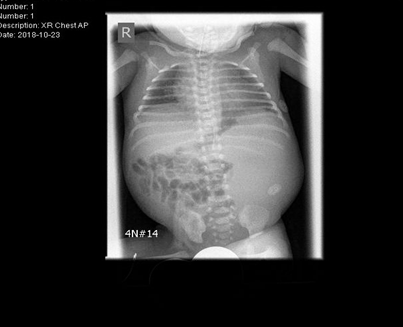

The initial examination showed small for age newborn, his growth parameters were all below 3rd centile donating intrauterine growth restriction. Grossly dysmorphic with wrinkled skin, flexed posture, abnormal head shape, high forehead, depressed nasal bridge anteverted nostrils, low set ears, micrognathia, proptosis, thick eyelashes and eyelids, partial syndactyly of 2nd and 3rd toes bilaterally with flattened feet and hands. The abdomen was bulging with palpable hard left upper quadrant mass, about 4cm, liver edge also felt below costal margin. The newborn was connected to mechanical ventilation for one day, extubated to CPAP, weaned to nasal cannula for another 3 days then he was off respiratory support till discharge. First x ray showed homogeneous soft tissue opacity occupying the left abdominal cavity pushing the bowel loops to the right side most likely the left enlarged kidney(Figure 1). Ultrasound scan revealed average size of both hepatic lobes with smooth surfaces, coarse hepatic parenchymal texture with diffuse periportal thickening, and extensive thick GB sludge. The Left Kidney was hugely enlarged Multicystic dysplastic with multiple sizable cortical cysts. It measures 6.7x3.8cm; right kidney was normal (Figure 2).

Figure 1 Chest and abdomen X ray showing homogeneous soft tissue opacity is occupying the left abdominal cavity pushing the bowel loops to the right side.